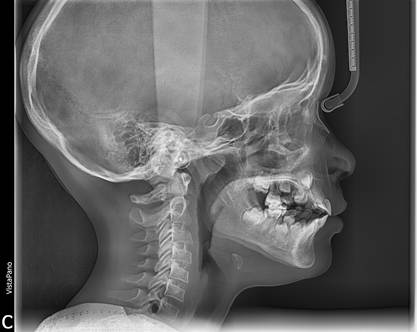

Figura 11. En la telerradiografía lateral de cráneo muestra una clase I esqueletal.